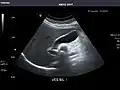

Abdominal Ultrasound (Full Exam)

STRUCTURED REPORT

(Technique: Transabdominal ultrasonography; Device: Toshiba Aplio XG)

Liver: Diffusely homogeneous and normal in echogenicity. No focal mass or contour nodularity. No intrahepatic biliary ductal dilatation.

Portal Vein: Patent main portal vein.

Gallbladder: No stones, wall thickening, or pericholecystic fluid.

Common Bile Duct: Nondilated measuring 1.3 mm at the level of the porta hepatis.

Pancreas: Visualized portions unremarkable.

Spleen: Normal in size.

Kidneys: Right and left kidneys measure 11.5 cm and 12 cm in length respectively. No hydronephrosis. Small left lower pole kidney cyst.

Ascites: None.

Aorta: Visualized portions normal in caliber, 16 x 15 mm.

IVC: Normal.

IMPRESSION:

Normal abdominal ultrasound.